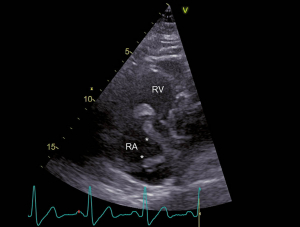

Ein 52-jähriger Patient musste sich wegen eines bronchialen Plattenepithelkarzinoms einer linksseitigen Unterlappenresektion unterziehen. Einige Tage postoperativ klagte der Patient plötzlich über starke Schmerzen im rechten Bein. Ferner bestand eine zunehmende Dyspnoe. Es zeigte sich im ischämischen rechten Bein ein ausgedehnter arterieller Gefässverschluss, welcher durch einen komplexen notfallmässigen Eingriff mit Thrombendarterektomie und Thrombektomie behandelt werden konnte. Die weiteren Abklärungen ergaben den Nachweis von tiefen Beinvenenthrombosen und von ausgedehnten beidseitigen Lungenembolien. Im Labor zeigte sich eine Thrombozytopenie und es wurde die Diagnose einer heparininduzierten Thrombozytopenie Typ II gestellt. Entsprechend wurde die Antikoagulation auf Bivalirudin umgestellt. Im Rahmen der Untersuchungen wurde eine transthorakale Echokardiographie durchgeführt. Hierbei zeigte sich ein dilatierter, exzentrisch hypertropher rechter Ventrikel (Abb. 1) und es fanden sich Zeichen einer ausgeprägten pulmonal-arteriellen Hypertonie (Abb. 2). Im rechten Vorhof zeigte sich ein grosser Thrombus, welcher am interatrialen Septum adhärent zu sein schien (Abb. 3). Ein Teil des Thrombus prolabierte durch die Trikuspidalklappe in den rechten Ventrikel (Abb. 4). Es wurde interdisziplinär entschieden, den grossen ‘Thrombus-in-Transit’ nach Stabilisierung des Patienten operativ zu entfernen. Die intraoperativ durchgeführte transösophageale Echokardiographie liess erkennen, dass der Thrombus nun durch ein persistierendes Foramen ovale (PFO) in den linken Vorhof prolabierte (Abb. 5). Bei der operativen Entfernung zeigte sich, dass der Thrombus in Fäden der Valvula Eustachii verfangen war (Abb. 6), was eine weitere Migration des Thrombus verhinderte. Der Anteil, welcher durch das PFO prolabierte, liess sich ohne Widerstand herausnehmen. Nach Entfernung des Thrombus wurde das Foramen ovale verschlossen. Die Operation verlief erfolgreich. Nach initial protrahiertem Verlauf erholte sich der Patient sehr gut und es zeigte sich eine deutliche Regredienz der pulmonal-arteriellen Hypertonie. Die Antikoagulation mit Bivalirudin wurde in der Folge auf Marcoumar umgestellt; es kam zu keinen weiteren thromboembolischen Komplikationen.

Abb. 3: RV-modifizierter apikaler Vierkammerblick Im rechten Atrium zeigt sich ein grosser, zweischenkliger Thrombus (*), welcher am interatrialen Septum adhärent zu sein scheint (Pfeil). RV = rechter Ventrikel und RA = rechtes Atrium.

Abb. 4: RV-modifizierter apikaler Vierkammerblick Erneute Darstellung des grossen rechtsatrialen Thrombus (*), wobei in diesem Bild der grössere der beiden Schenkel durch die Trikuspidalklappe in den rechten Ventrikel prolabiert (Pfeil). RV = rechter Ventrikel und RA = rechtes Atrium.